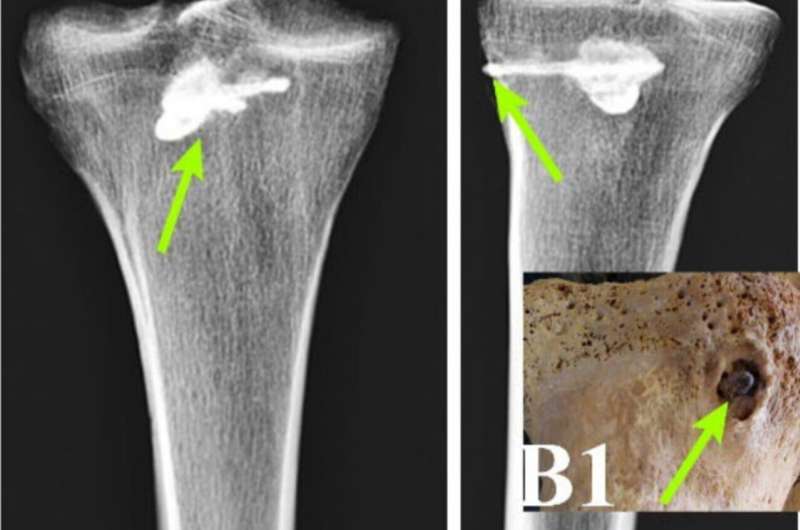

Redaktorların qeydləriSümük və gömülü oxun müxtəlif şəkilləri. Kredit: Eghdami et al. 2025

X-şüaları flüoresan, kvantometr analizi və KT taramalarından istifadə edərək, fərddə sağ baldır sümüyünə gömülmüş metal əşyanın olduğunu müəyyən edə bildilər.

Müayinə zamanı məlum olub ki, bu, uzunluğu 44 mm, eni 15 mm olan üç ağızlı metal ox ucudur.

Ox ucu digər Parfiya oxları ilə uyğunluğu ilə diqqət çəkir.

Əlavə təhlillər göstərdi ki, zərbədən bir müddət sonra ox ucu ətrafında sıx sümük toxuması əmələ gəlməyə başlayıb. Bununla belə, okun tibial vərəmdə sümüyə nüfuz etdiyi sahə istisna olmaqla, infeksiya əlamətləri və ya yeni sümük əmələ gəlməsi aşkar edilməmişdir.